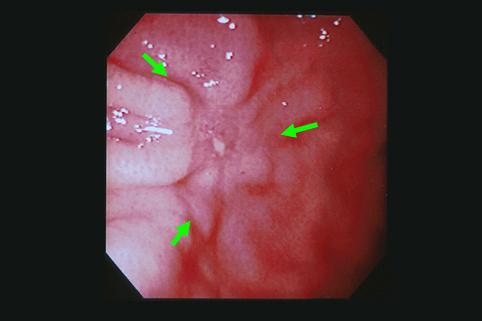

질환(병리주체)의 분류 악성 상피성종양/선암

부위(장기별) 위(부위)/체부

검사방법 내시경

종양의 육안분류 0형(표재형)/IIc형(IIc)

종양의 최대경(밀리미터) 25~29

종양의 심달도 m